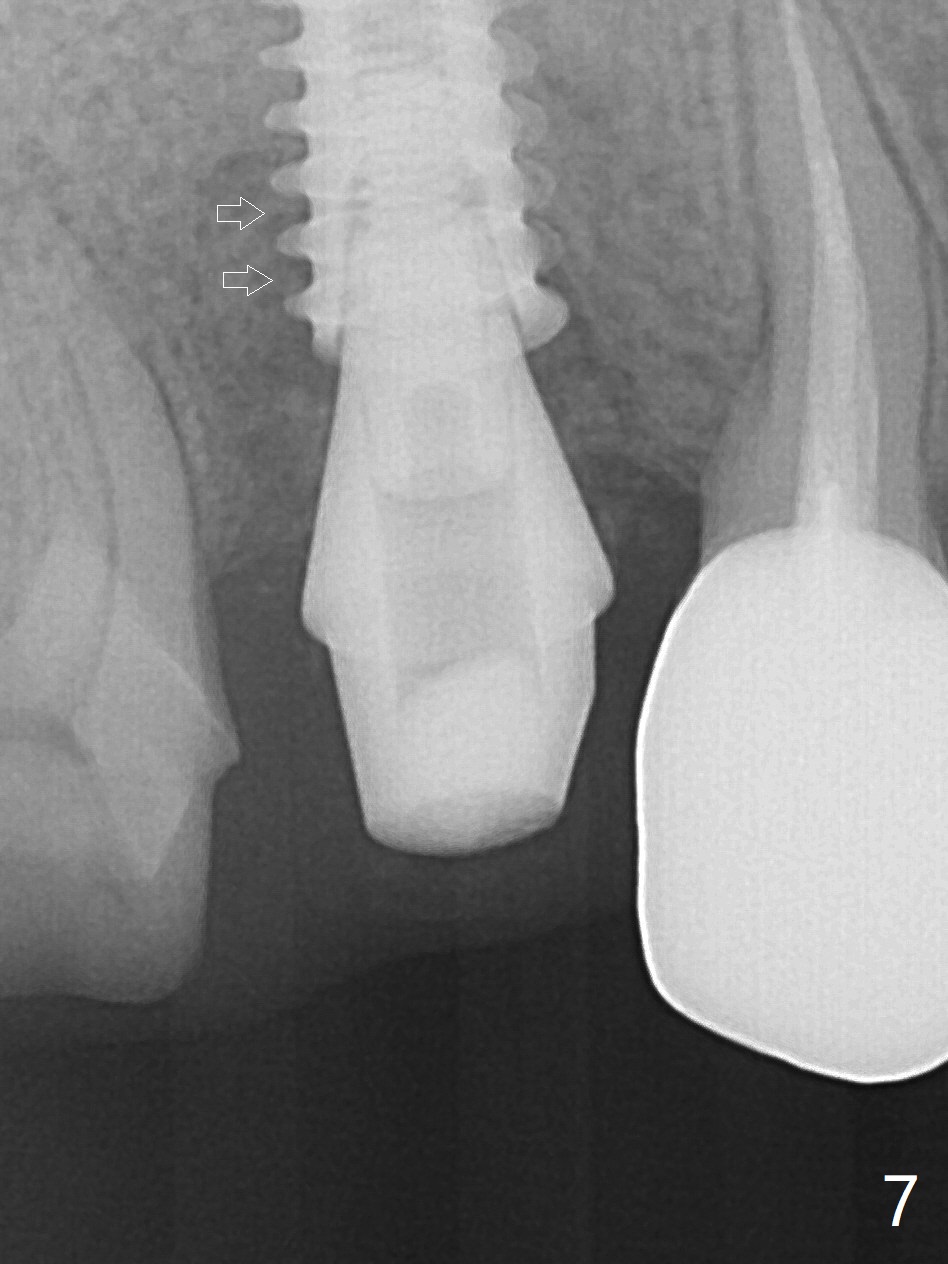

When the tooth #4 with vertical root fracture is extracted, the socket is large, approximately 6x10x10 mm (Fig.1 (mesiodistal x buccopalatal width x depth)). Osteotomy is established in the middle of the socket with 2 mm initial drill for 7 mm, 2.8 and 3.6 mm rounds drills (from DIO Sinus Master Kit) for < 7 mm, and 3.0 and 3.8 mm Magic Expanders. A 4x11 mm dummy implant is placed with insertion torque of 30 Ncm (Fig.2,3 (^: sinus floor)). There is a gap between the socket wall and the implant (*). To reduce the gap and periimplantitis, a 5x11 mm IBS implant is placed with insertion torque > 50 Ncm after further osteotomy using Magic Drills (Fig.4,5). Following placement of 5.5x4(4) mm abutment (A) and bone graft (data not shown), a splinted provisional is fabricated at #3 and 4. The provisional is stable 3 months postop (Fig.6,7). The peri-implant gaps (Fig.4,5) seem to disappear (Fig.6) with the help of bone graft. Bone graft appears to remain between the implant fins (Fig.7 arrows). Impression is taken 4.5 months postop (Fig.8,9). The abutment dislodges 4 months post cementation. After retightening, there is clearance for shim after use of 2 layers of thick articulating paper. Is the abutment screw too short? Or Titanium V is too hard for welding? The abutment/crown dislodges again 1 year 3 month post cementation; it appears that the fact that the implant is placed deep contributes to abutment screw loosening (Fig.10,11). An abutment screw will be buried inside the implant well 10 days post initial retightening.